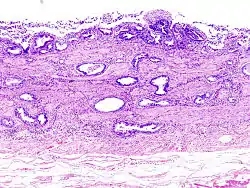

Gallbladder adenocarcinoma lymphatic invasion histopathology

Incidentally discovered gallbladder cancer (adenocarcinoma) following a cholecystectomy.